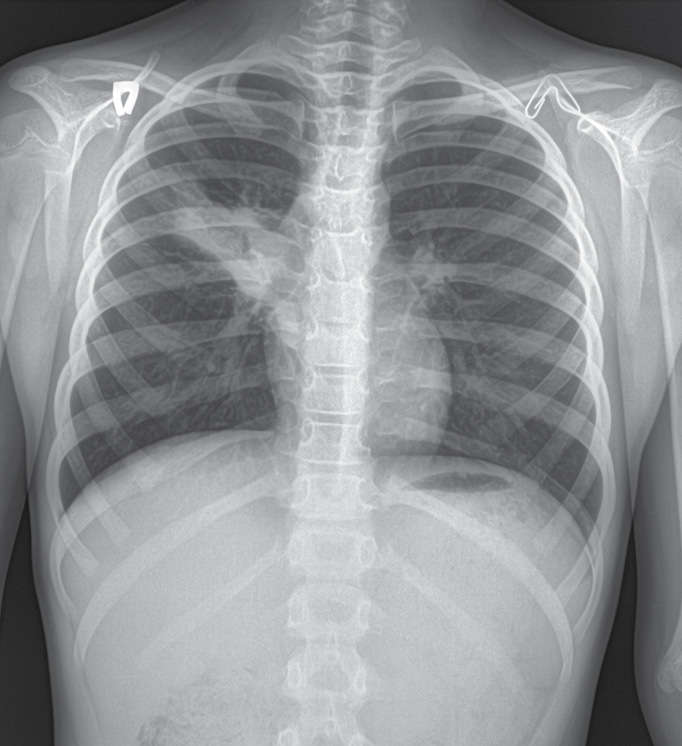

27.04 на рентгенограмме органов грудной клетки (ОГК) в двух проекциях определялось выраженное неоднородное затемнение легочной ткани по типу пневмонической инфильтрации в проекции S2–S3 справа. Легочный рисунок в зоне инфильтрации не прослеживался. Подчеркнута и подтянута кверху горизонтальная междолевая плевра. Тень сердца размыта в верхних отделах справа. Контуры диафрагмы четкие, ровные, плевральные синусы свободны (рис. 1).

Рис. 1. Рентгенограмма ребенка Н., 8 лет 7 мес., 27.04

Fig. 1. X-ray of a child N., 8 years 7 months, 27.04